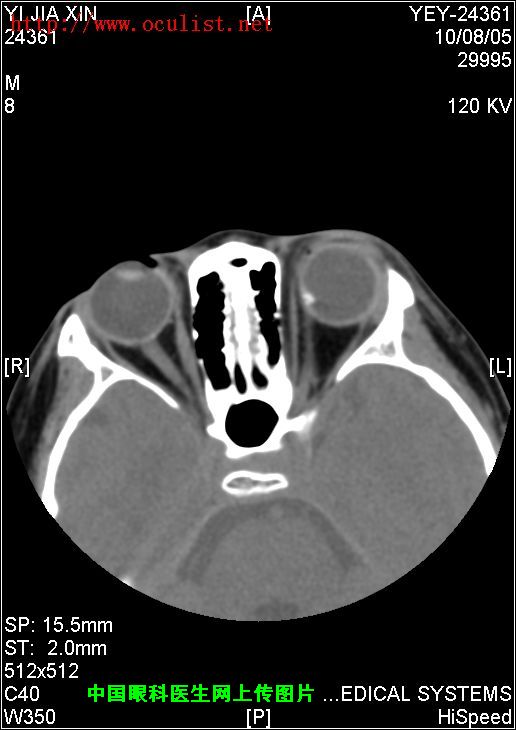

患者男,9岁,发现左眼外斜9年

患者男,9岁,发现左眼外斜9年,检查:左眼视力0.01(矫正不应),左眼外斜400,角膜、晶状体未见异常,眼底如下图,CT如下图,RMI暂无,请分析一下该患儿的诊断?

眼底图和CT片: